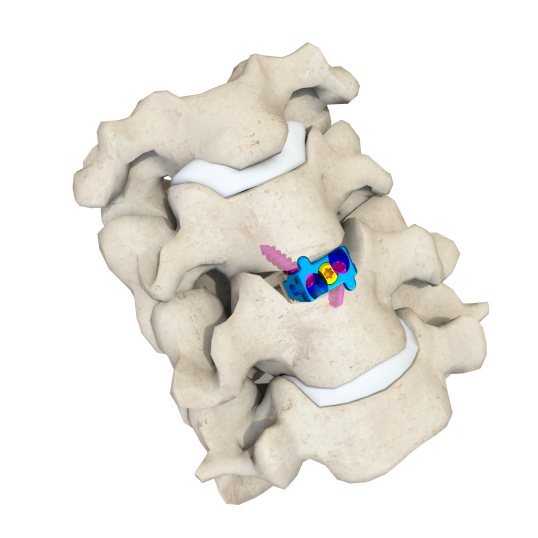

SAGI自穩定(ding)頸椎融(rong)合器

符合國人(ren)解剖(pou)尺寸設計

為臨床提供個性化(hua)處理(li)鉤椎關節的解(jie)決(jue)方案

減少(shao)椎體下(xia)沉(chen)幾率

降低脊(ji)髓硬膜外血腫風險

可(ke)變角度(du)螺釘(ding)設計,操(cao)作便捷

螺(luo)釘冠狀面(mian)擺(bai)角(jiao)-1.5°~11.5°,頭尾向擺(bai)角(jiao)36°~44°,術中(zhong)置(zhi)釘更加便(bian)捷

更微(wei)創

不需為(wei)螺釘置入預留(liu)額外空間(jian),最小切口從2.5cm縮小至2.0cm左右

更適配(pei)脊柱內鏡下操(cao)作(zuo)理念,實現Endo-ACDF